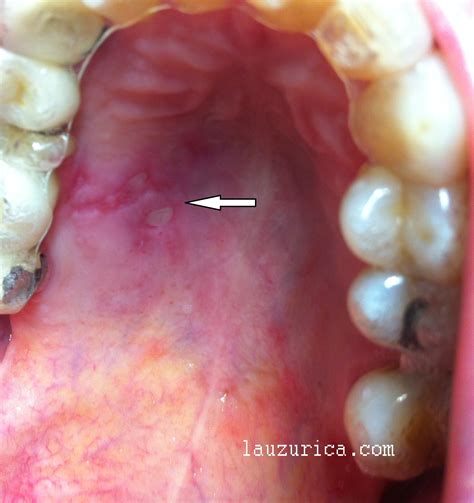

Las llagas en el paladar o aftas bucales suelen aparecer en los tejidos blandos de la boca, incluyendo el paladar. Son pequeñas heridas que están expuestas y abiertas. Suelen tener un color amarillento o blanquecino muy característico. Pese a que puedan parecerse a las calenturas o herpes, hay que saber diferenciarlos. Las llagas orales no son contagiosas en absoluto, sin embargo, un herpes bucal es muy contagioso.

Cuando las úlceras bucales aparecen en el paladar, pueden presentarse en dos lugares:

- Paladar duro: No es muy común que las aftas aparezcan en esta zona de la boca. En las situaciones en las que las lesiones se presentan aquí lo más probable es que se deba a una consecuencia clara. Normalmente se producen por la aparición de infecciones bucales o como consecuencia de una prótesis dental que no está bien colocada. Acudir al dentista si esto ocurre es muy importante.

- Paladar blando: Son mucho más comunes las llagas en el paladar blando. Estas aftas aparecen debido a causas variadas, exactamente igual que ocurre con la formación de llagas en otras zonas de la boca, como los labios, las encías, las mejillas o la lengua.